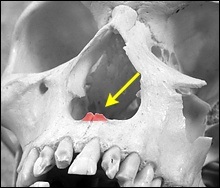

Mielőtt nagyobb acanthion. Ez az, amit úgy néz ki, a művelet során. Az ábrán a jobb ez sárga színű. Acanthion columella található, közvetlenül alatta, ahol a felső ajak határos az alapja az orrát.

Része a gerinc, amelyeket el kell távolítani jelzi a kék vonalon. Removal végezzük vésővel.

A felső és az alsó képen látható két legkiemelkedőbb nazális gerinc, a jobb kilátás bővítették segítségével horgokat.